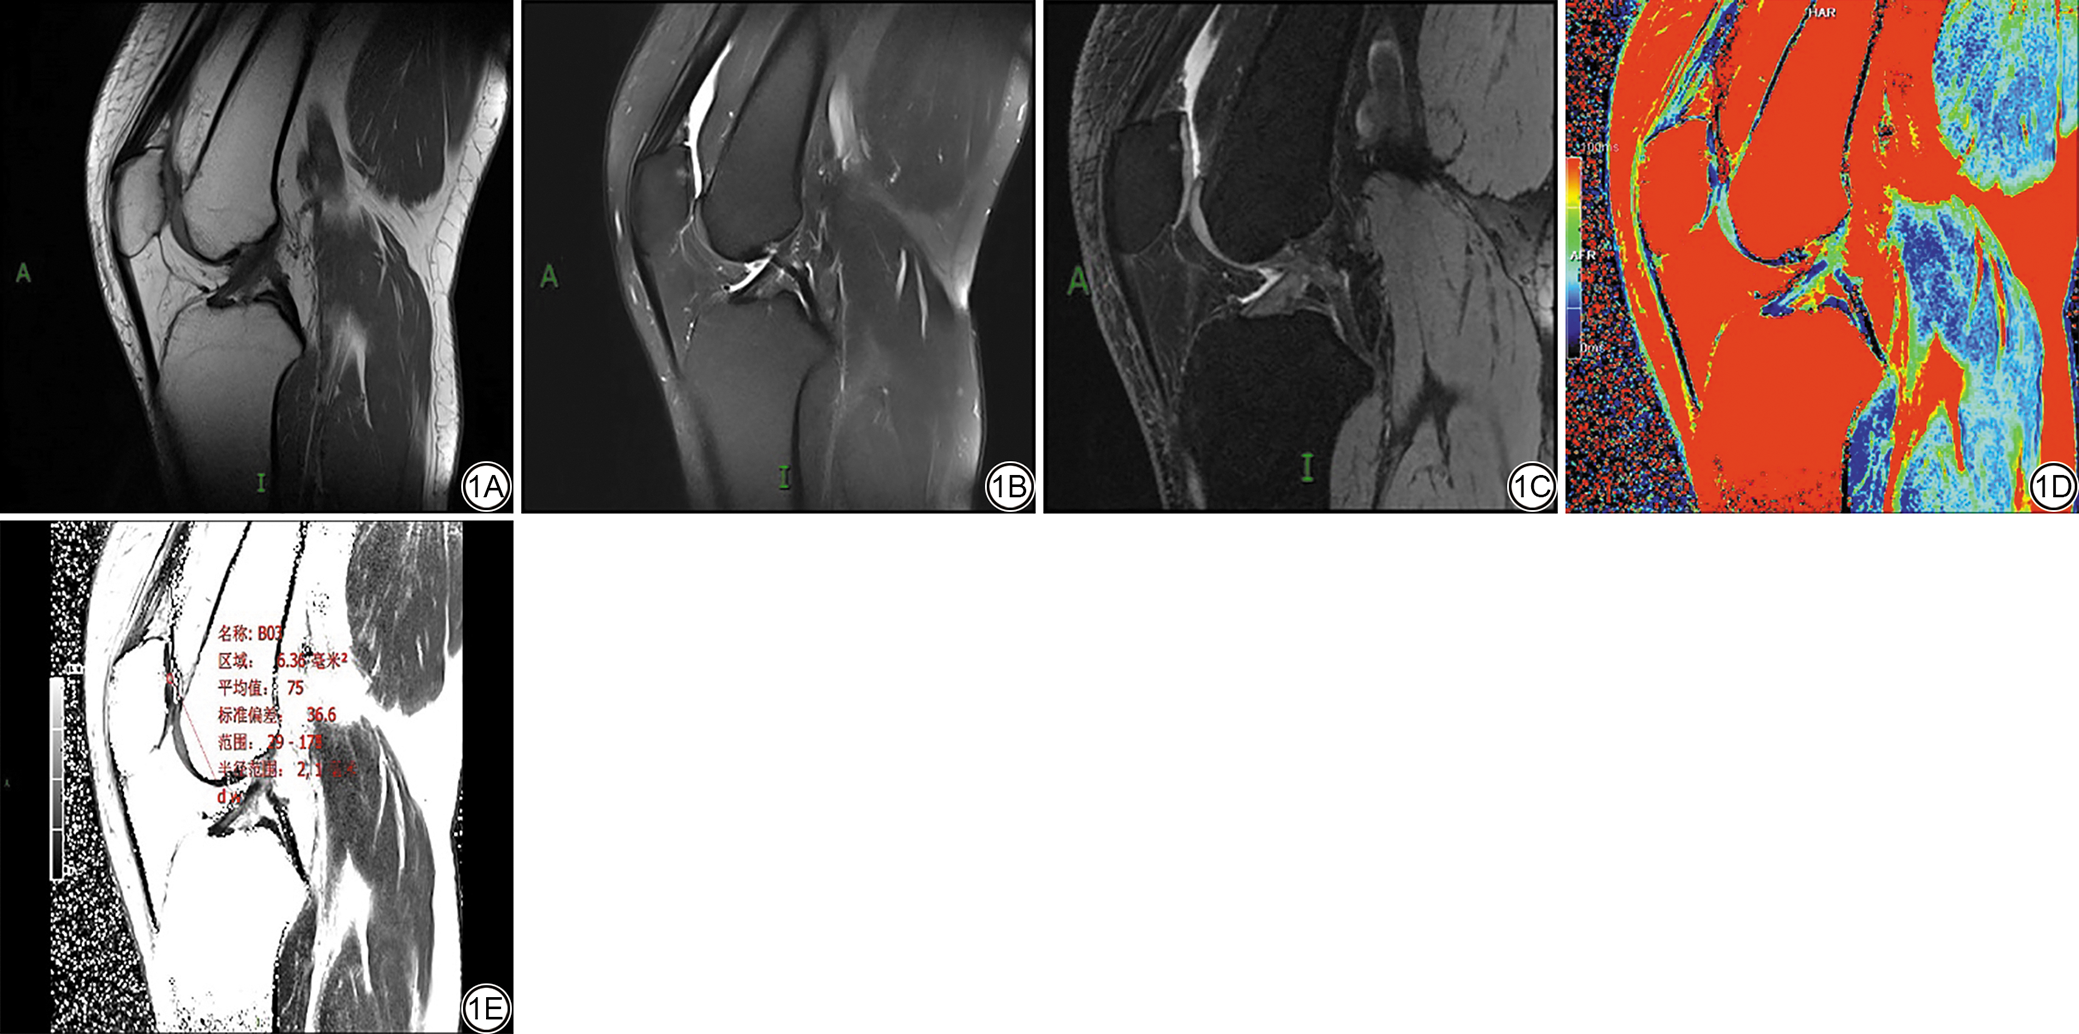

所有图像由两名从事放射诊断专业10~15年的副主任医师采取双盲法分别对膝关节X线负重位片进行KOA KLG、对膝关节MRI图像(包括膝关节常规图像、T2 mapping矢状位及3D SPGR矢状位)进行PFJ髌软骨损伤综合判读并进行Recht分级,如遇分级不同,则需协商达成一致(两位医师的一致性分析方法采用Kappa一致性检验)。所有被试负重位X线片根据KLG评分[10]共分为4组:KLG 0~1级、KLG 2级、KLG 3级、KLG 4级;对所有被试同侧膝关节MRI图像进行PFJ Recht评分,如图1所示。PFJ软骨损伤共分为4组:Recht Ⅰ级、Recht Ⅱ级、Recht Ⅲ级、Recht Ⅳ级。由上述其中1名从事放射诊断专业10余年的副主任医师应用西门子工作站软件在膝关节矢状位T2 mapping伪彩图相对应的原始灰度图像中勾画髌软骨感兴趣区(region of interest, ROI),并测得T2值(同一图像由同一观察者勾画三次、取三次测量的平均值为最终T2值,三次ROI勾画均在重新加载图像后再进行测量),ROI定位层面选择正中矢状位层面,ROI为直径约3~5 mm圆形区域,注意避开相邻结构,提高ROI T2值精准度,如图1D~1E所示。

图1  男,43岁,髌股关节髌软骨显示及ROI勾画示意图。1A:T1WI矢状位序列;1B:FS-T2WI矢状位;1C:3D SPGR矢状位;1D:T2 mapping序列伪彩图(提示髌软骨蓝色背景中出现红色及黄色异常信号带,直观显示软骨损伤);1E:在图1D相同层面矢状位原始图测量ROI T2值,显示病变区T2值为75 ms。ROI:感兴趣区;FS:脂肪抑制;3D SPGR:三维扰相梯度回波。

Fig. 1  Male, 43-year-old, schematic diagram of patellar cartilage display and ROI delineation in the patellofemoral joint. 1A: T1WI sagittal sequence; 1B: FS-T2WI sagittal sequence; 1C: 3D SPGR sagittal sequence; 1D: T2 mapping sequence pseudo-color map (the pseudo-color map shows red and yellow abnormal signal bands against a blue background in the patellar cartilage, visually indicating cartilage damage); 1E: Original sagittal image of the same slice as Figure 1D for ROI T2 value measurement, showing a T2 value of 75 ms in the ROI. ROI: region of interest; FS: fat-suppressed; 3D SPGR: 3D spoiled gradient recalled echo.